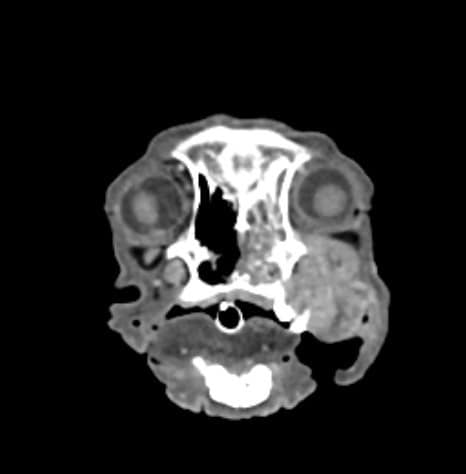

狗狗阿旺 因為口腔團塊 流鼻血 被轉診至築心做進一步檢查

病理切片診斷為惡性骨肉瘤

電腦斷層檢查發現左上牙齦 鼻甲骨 上顎骨到眼窩 都被侵犯